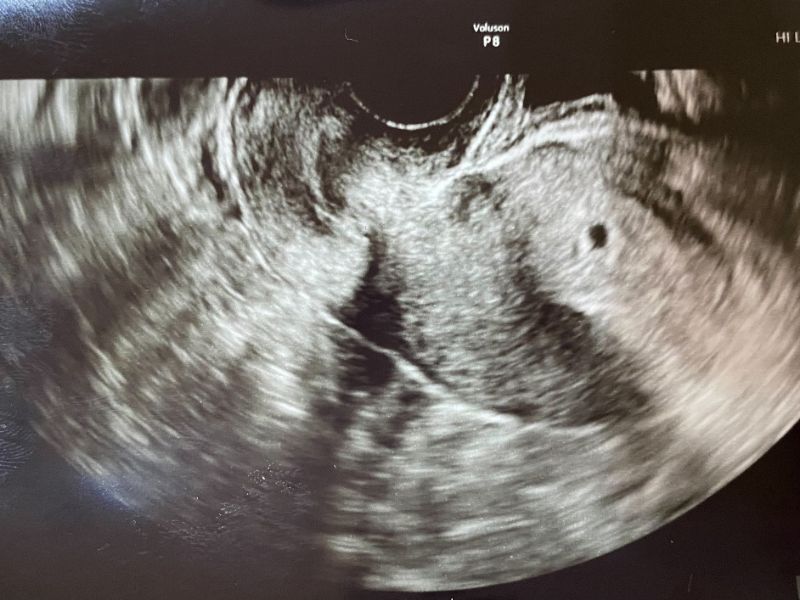

そんなことを思っていたら娘からLINE 三人目の孫やで、と超音波画像の右側に黒い点があった。 5週目で次の検査は再来週。ツワリはあるけどご飯は食べれているとのこと。 出産のときに去年の脊髄手術の影響はあるのだろうか?